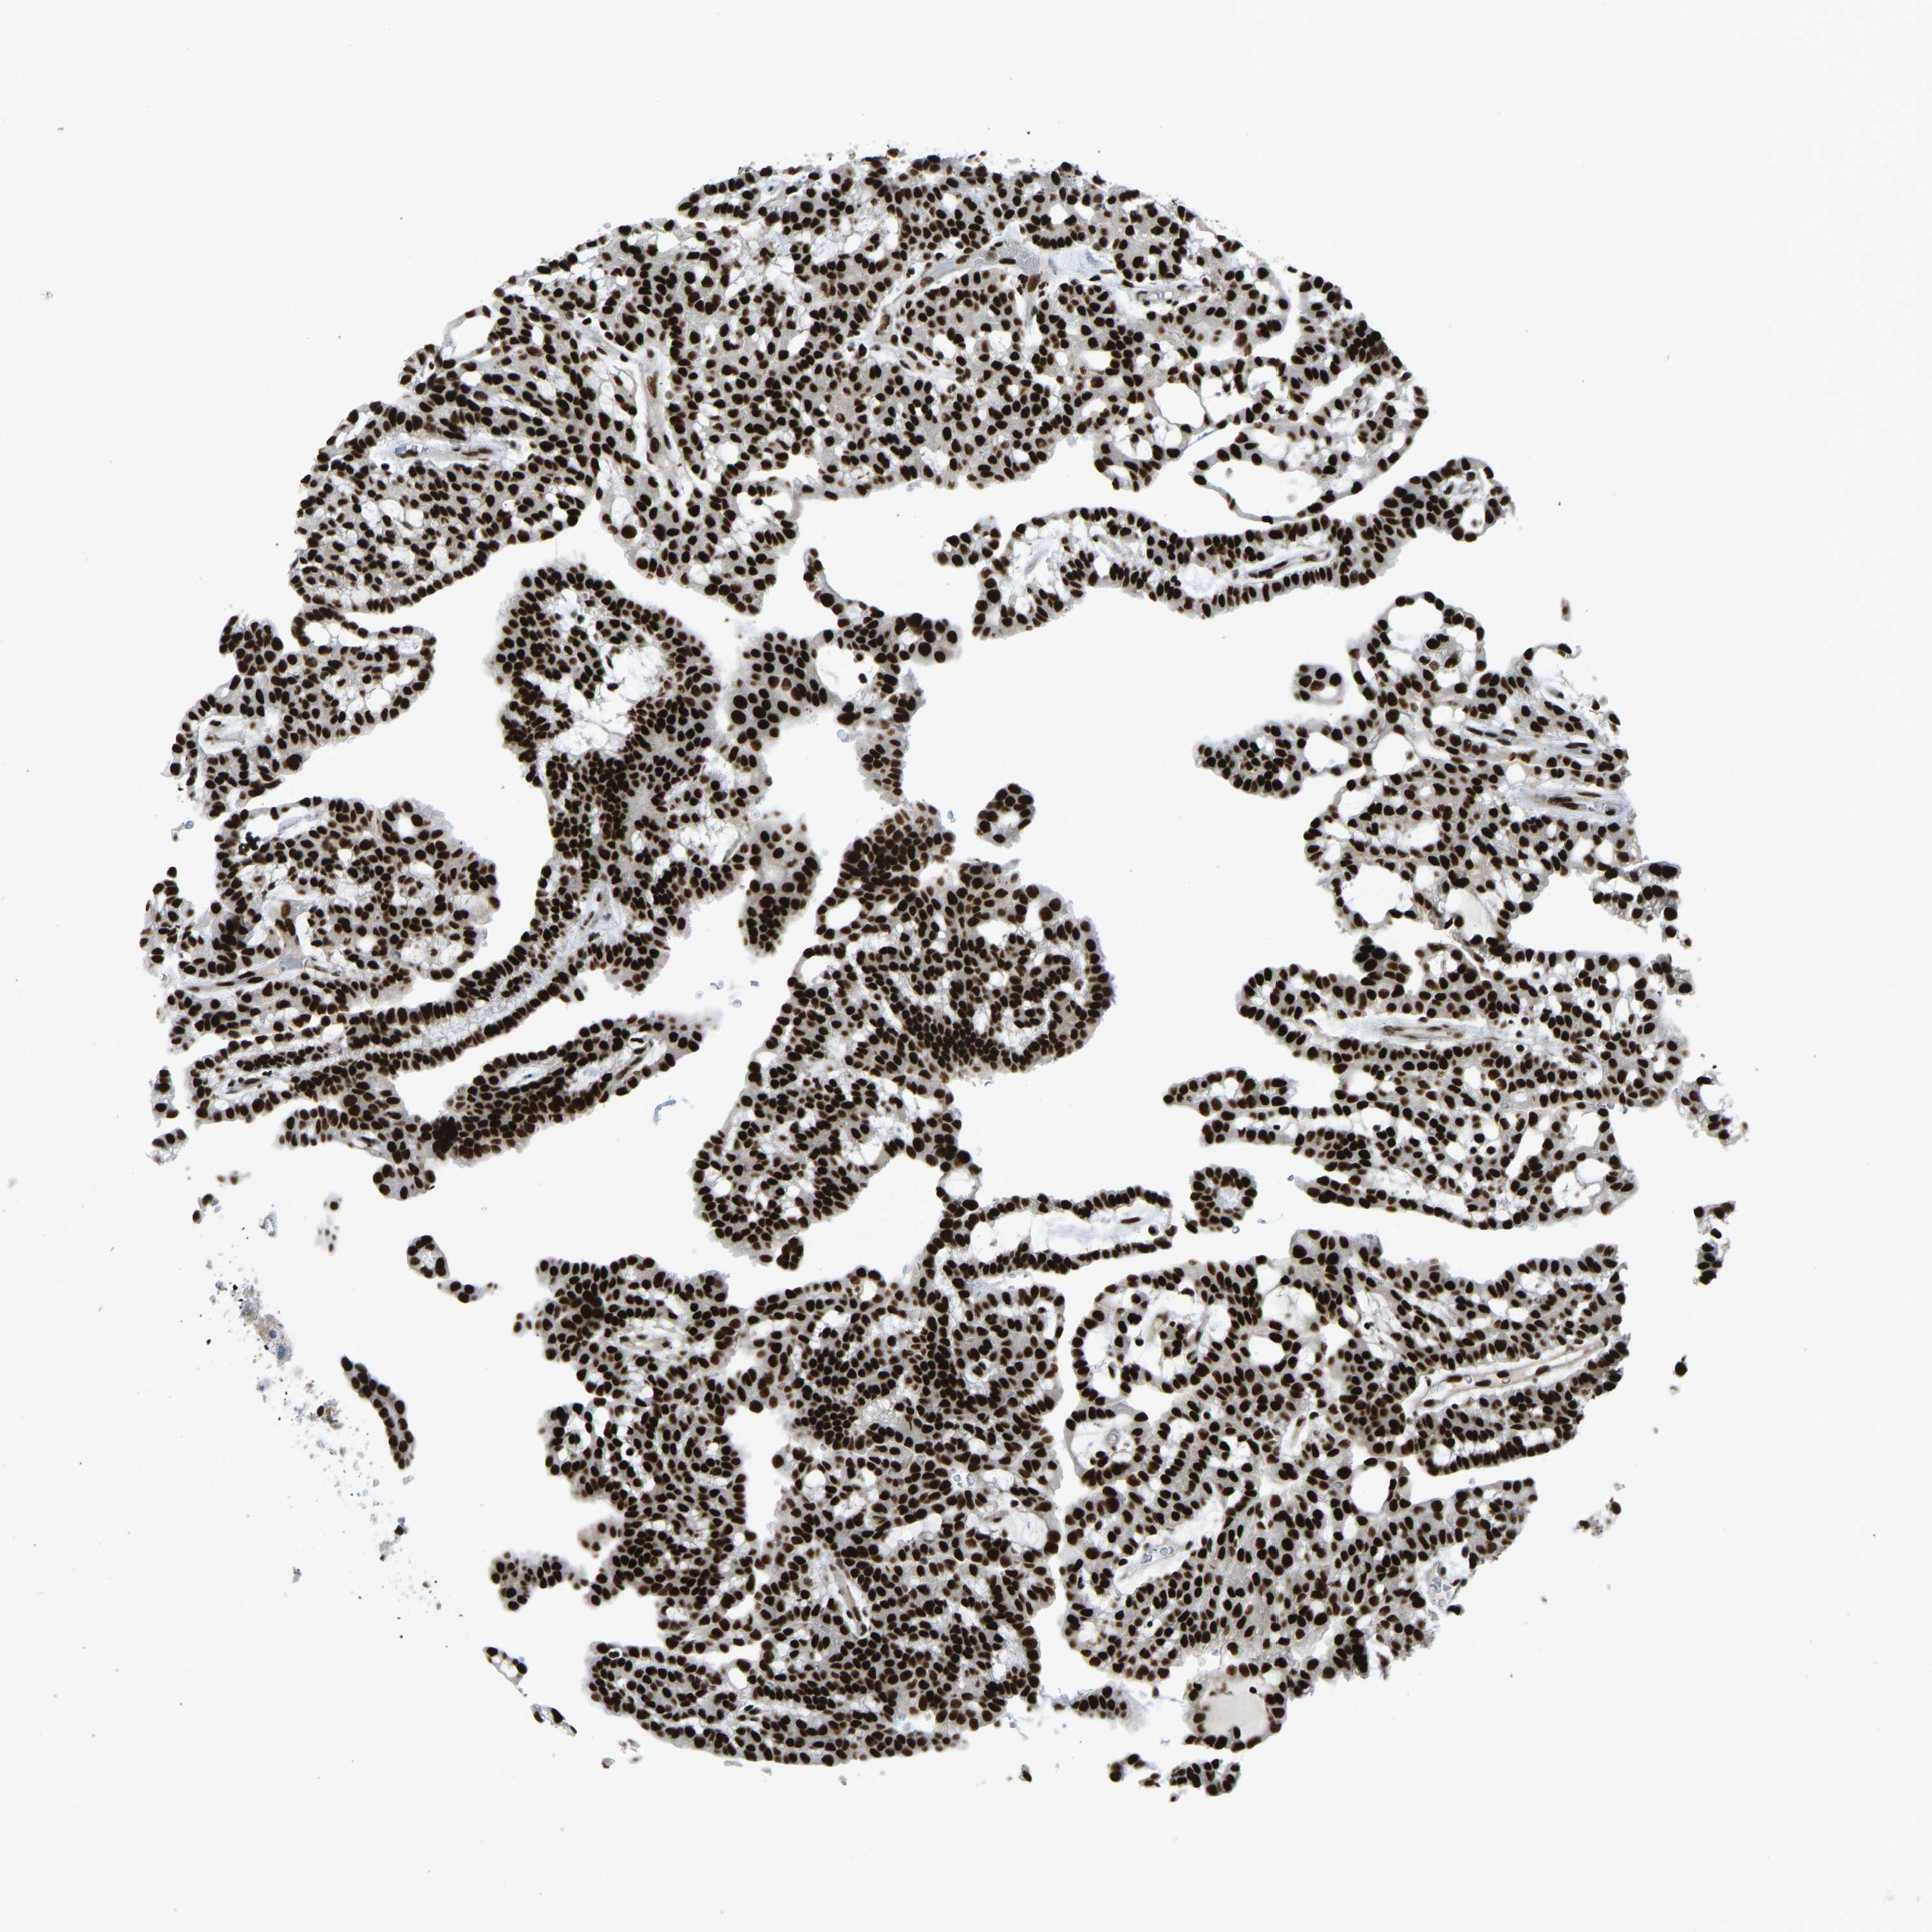

CANCER RENAL CANCER Show tissue menu

Renal cancer

Kidney renal clear cell carcinoma